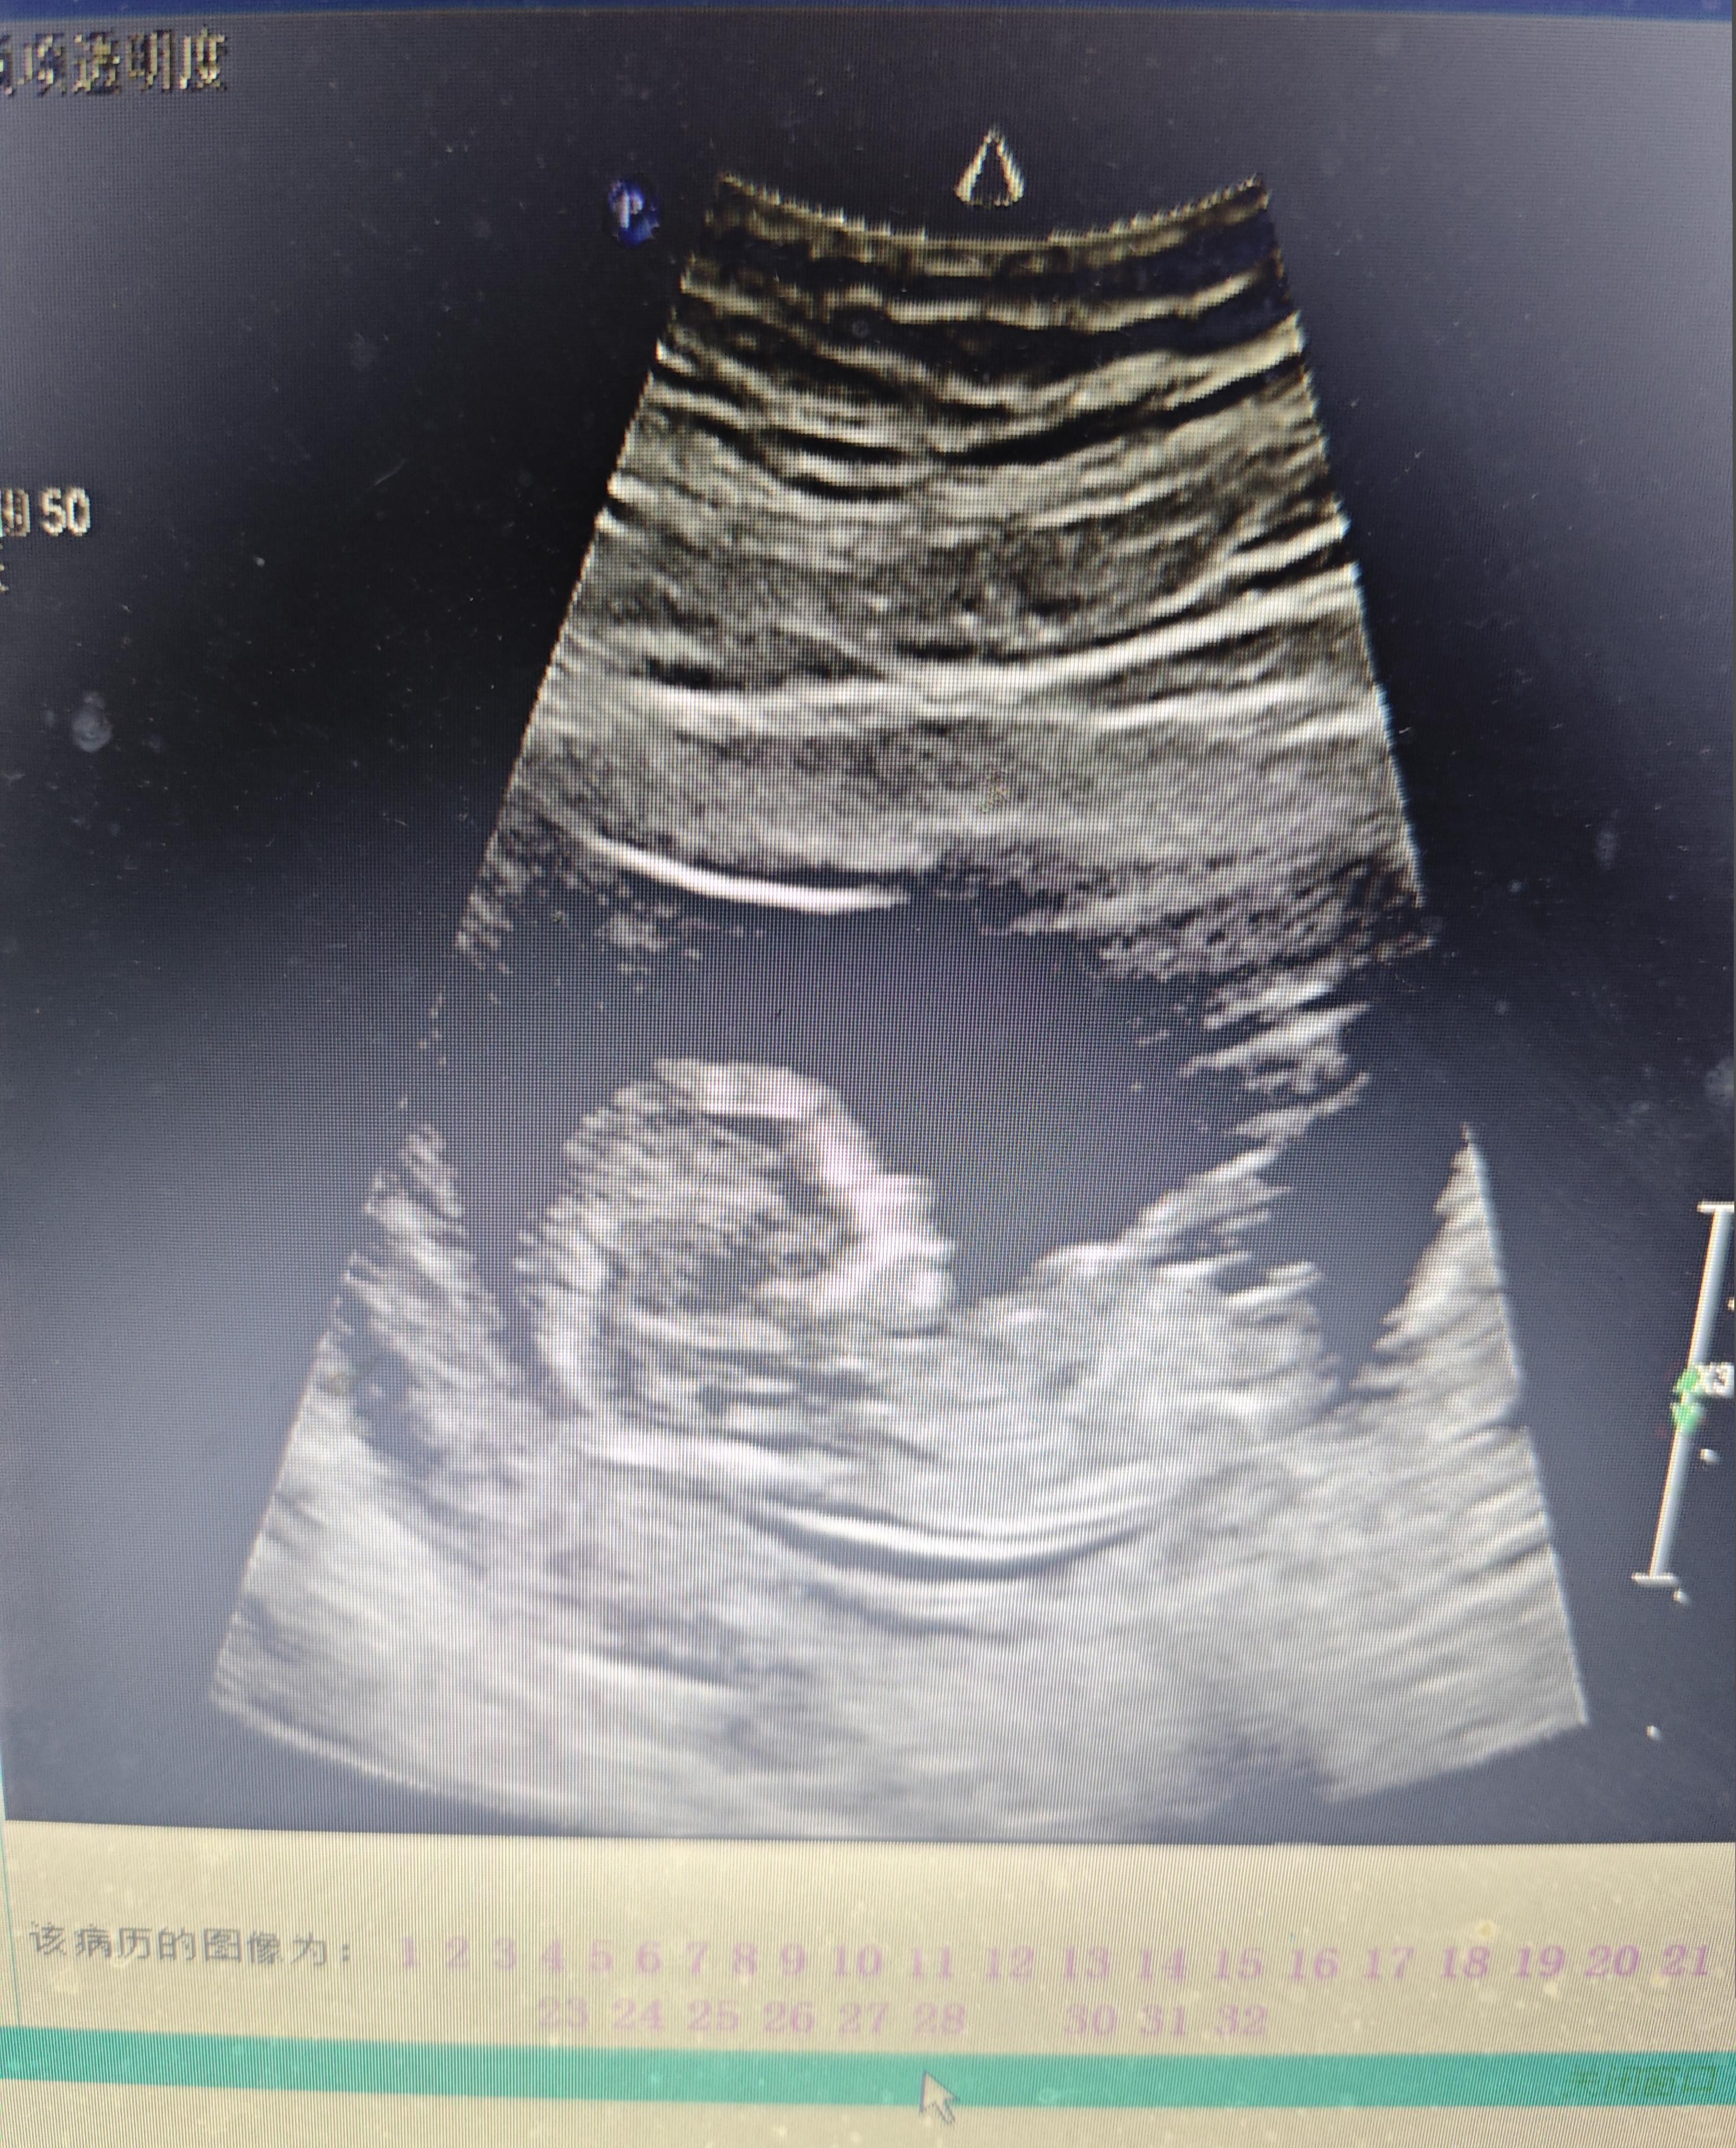

孕12周 NT检查

第一次 8:15 站着

第二次 8:52 趴着

第三次 10:45 坐着

第四次 11:35 逮不着他,太活跃了